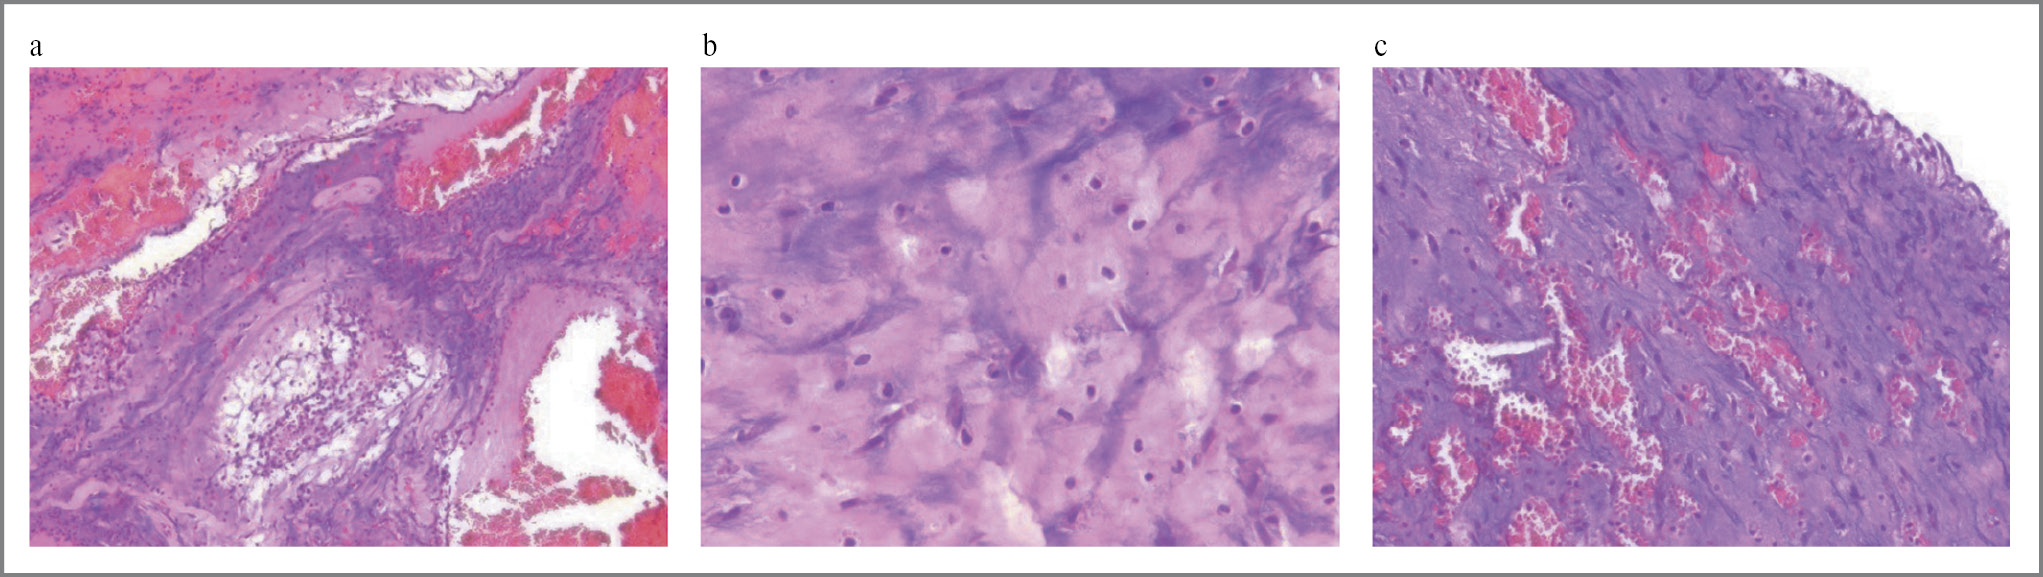

По результатам гистологического анализа (рис. 6) обнаружены фрагменты опухолевого материала с миксоматозной рыхловолокнистой стромой, мелкими очагами и цепочками из мелких полигональных опухолевых клеток с эозинофильной цитоплазмой с мелкими гиперэхогенными ядрами, обширные кровоизлияния с отложением гемосидерина, скоплениями гемосидерофагов, лимфоцитарная и гистиоцитарная инфильтрация, многочисленные сосуды капиллярного и синусоидного типа, часть из них резко расширена, содержит кровь, участки фиброза. Заключение: миксома ЛП.

Рис. 6. Гистологическая картина миксомы: a – ×10; b, c – ×20.

Fig. 6. Histological picture of myxoma: a – ×10; b, c – ×20.